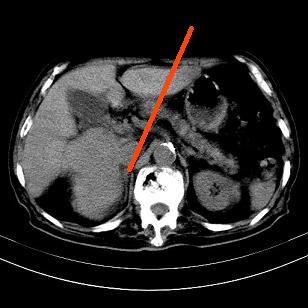

标题: CT19407:肝内还是肝外原发性肿瘤??

男,63岁,高血压病史40余年,

来源-右侧肾上腺。

考虑右侧肾上腺巨大占位;恶性?

肝内多发低密度找;转移瘤?

考虑右肝后叶肝癌伴多发肝内转移

考虑右肝后叶肝癌(部分外生)伴肝内多发性转移;右侧肾上腺区恶性肿瘤并肝转移待排。

考虑右侧肾上腺肿瘤并肝内多发转移。右侧肾上腺呈“八”字形,包括内侧枝及外侧枝,内侧枝受压,考虑外侧枝原发肿瘤。”